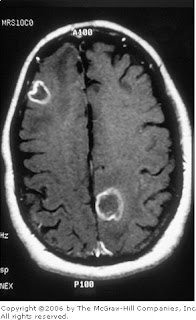

Mri Brain T1 Axial View Showing Multiple Ring Enhancing Lesions

Brain Mri With Contrast Showing Multiple Ring Enhancing Lesions